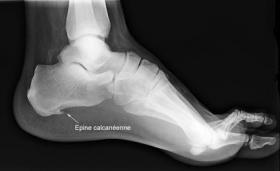

Epine calcanéenne

L'épine calcanéenne est une excroissance osseuse pointue qui se forme sur la face inférieure de l'os du talon appelé calcanéeum. Cette excroissance résulte de l'inflammation du fascia plantaire, la membrane fibreuse épaisse qui relie le calcanéum (os du talon) aux phalanges du pied.

La fasciite plantaire (ou aponévrosite plantaire) désigne l'inflammation du fascia plantaire (voir les causes plus bas). Ce phénomène inflammatoire résulte de micro-traumatismes au point de jonction de cette membrane avec le talon, lorsque le fascia plantaire est trop sollicité (surcharge). Lorsque l'inflammation perdure et devient chronique, un processus de guérison peut s'enclencher spontanément : des cellules osseuses se forment alors pour soulager le fascia plantaire de la surcharge excessive. Une petite épine osseuse horizontale, qui pousse dans le sens de la marche, apparaît. Sa présence est mise en évidence par un simple l' examen radiologique.